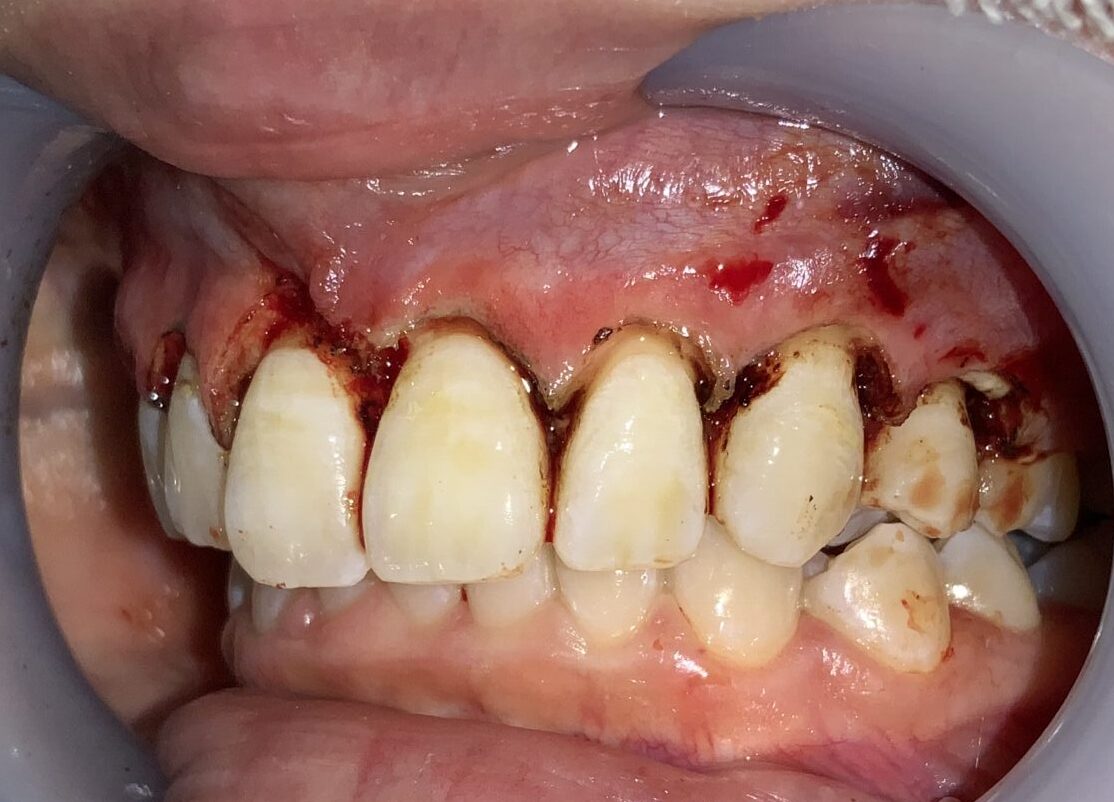

安全に切り取ることができる範囲がわかります。

さらに隣の歯も検査します。

こちらの歯は犬歯です。大きく切り取り過ると、八重歯になってしまうので、注意が必要です。

安全に切除できる範囲の歯ぐきを計測します。

反対側の歯の検査に移動します。

血液が出ているのは、局部麻酔の影響です。歯の検査の影響ではありませんので、ご心配なく、検査をお受けください。

歯ぐきの厚みや歯槽骨の状態も確認します。

この歯も歯ぐきが被っている量が相当あります。

最後に犬歯の検査をします。

犬歯もこのように小さな形ではなく、綺麗な形になります。

八重歯にならないように細心の注意をします。